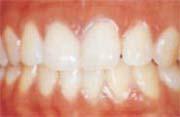

健康な歯肉

(1)三角形…歯と歯の間は鋭角

(2)明るくピンク色

(3)硬く弾力性あり